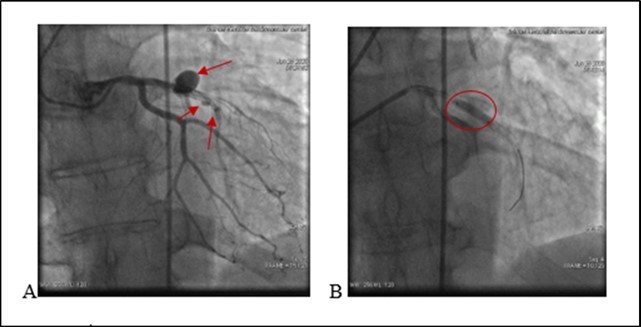

21.06.20 05:03 Am the patient complained chest pain. A drop in blood pressure and bradycardia was noted. T/A 80/60 mm Hg. There was no changes on echocardiography. No pericardial separation. No ST segment changes on ECG . Due to hemodynamic instability we decided to repeat a coronary angiography and it again revealed a medial segment stent thrombosis in LAD with multiple extravasations at proximal and medial segments Type III and II (see. Figure 3) -late perforation of coronary artery. At proximal segment pericardial hemorrhage provided pericardial hematoma with diameter 9-10 mm. At medial were visualized. During coronary angiography a patient’s condition deteriorated. Blood pressure dropped to T/A 60/40 mm Hg. A cardiac tamponade developed because of blood leak into pericardial space. A 3 mm balloon was inflated immediately in the site of rupture, with complete occlusion of vessel, stopping of a blood flow in the LAD and termination of extravasation into the pericardial space.

Figure 3.A. (21.06.2020) Second acute stent thrombosis and perforation Type III and II (red arrows) B. Balloon inflation in the site of rupture (red circle).

Deployment of covered stents was not purposeful due to highly suspected infection. A decision was made for urgent surgical treatment. A patient was urgently transferred to a cardiac operation theater surgical department with inflated balloon to eliminate a blood leakage in the pericardium. Ligating the coronary artery with removing stents, subsequent bypass grafting was performed, with removal of 500 ml of coagulated blood from the pericardial space. Post-surgery period remained stable. Leukocytes - 14.24 x10`3/μ L (N 4-10). A Pseudomonas Aeruginosa (multirresistent) - was positive after coronary wall tissue histomorphological examination. During hospitalization developed renal insufficiency.